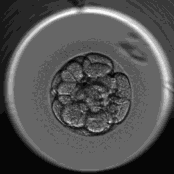

当胚胎发育到第3天时,胚胎师会通过胚胎细胞数、胚胎对称性及胚胎碎片率来综合评定一枚胚胎的质量。

这一关主要是通过胚胎评级来筛选出“高颜值”的胚胎,而评分低的胚胎则需面临淘汰的结局。